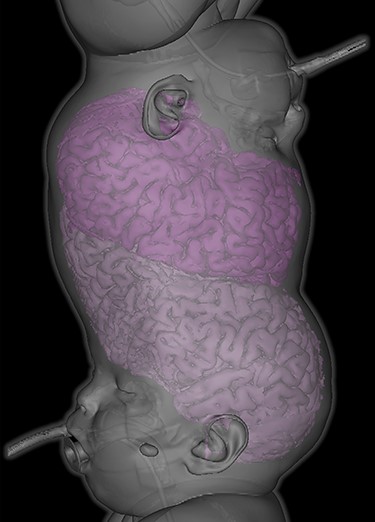

Male craniopagus conjoined twins were referred to our unit at 17 months old on 2 December 2019 from Antalya, Turkey. They were delivered at 32 weeks by caesarean section. We diagnosed total vertical craniopagus malformation, featuring continuous cranium and inter-twin axial facial rotation (Type II) [4], which can be appreciated on three-dimensional reconstruction (Fig. 1). There were no major ocular concerns reported by the parents.

Three-dimensional reconstruction demonstrating total vertical (Type II) craniopagus malformation.